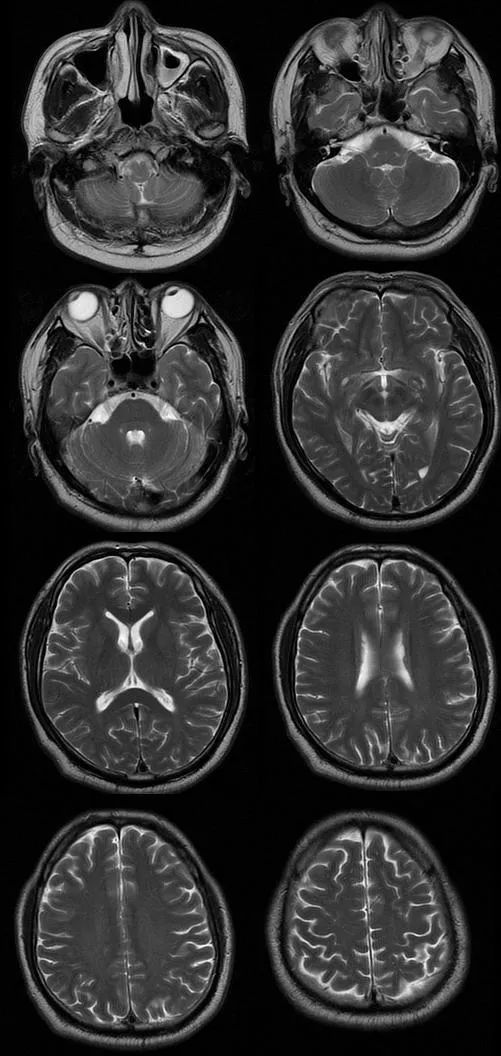

遗憾的是胸腰部 MRI 中 T1、T2、STIR 均未见明显异常,我们进一步完善头部 MRI,如下图:

T1

T2

T2FLAIR

从影像学可以看出 T2FLAIR、T1、T2 似乎也未见明显异常,此时该如何诊断,定位到底在哪里呢?